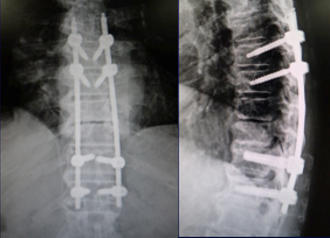

連続性に骨が癒合している間に骨が癒合していない部分があり、同部位で狭窄が生じ脊髄が圧迫されています。 -

経皮的椎弓根スクリューを用いたミスト手術で、低侵襲に脊椎を安定化し、神経症状は著明に改善しました。